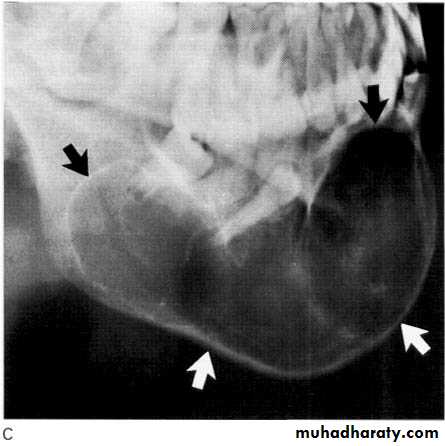

Odontogenic tumours Ameloblastoma

This is an aggressive but non-metastasizing tumour originating from remnants of the odontogenic epithelium of the enamel organ or dental lamina.•Site: Posterior body/angle/ramus of mandible, very occasionally involves the maxilla.

• Shape: — Multilocular,

— Occasionally monolocular in early stages

— Rarely honeycomb or soap-bubble appearance or multicystic

• Outline: — Smooth and scalloped

— Well defined

— Well corticated.

• Radiodensity: Radiolucent with internal radiopaque septa.